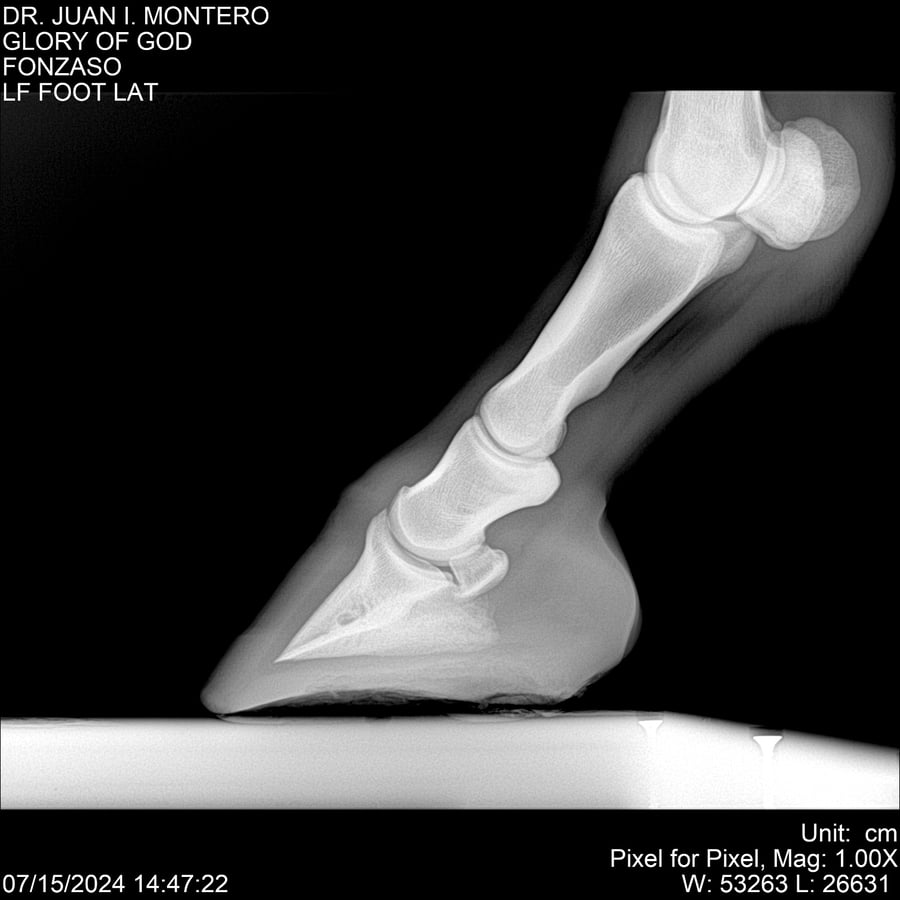

LOTE 10, GLORY OF GOD 🔥 🔥 🔥 Lote Anterior Volver al remate Lote Siguiente Ficha Contacto Montevideo - Ficha del Lote Identificador: #281389 Categoría: Yeguarizos Montevideo - 115 Visualizaciones ClicData Contacto Empresa: Abelenda N. R., Walter Hugo Nombre*: Teléfono* : E-mail* : Mensaje Enviar Registrese gratis Este contenido Exclusivo está disponible sólo para usuarios registrados Ingresar